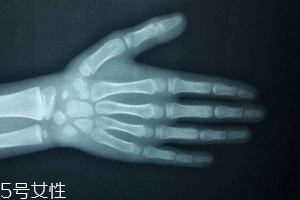

哪些人需要测骨龄?长太快警惕骨龄提前

》的解答。1.有必要测骨龄2.哪些人需要测骨龄?长太快警惕骨龄提前3.十六周岁还有没有必要测骨龄4.孩子有必要测骨龄吗1.应用1:和同龄孩子相差很多,区分“早长”或是“晚长”等。

2.应用2:剩余生长空间及性成熟度的判断。

3.应用3:预测儿童的成年身高(辅助判断是否需要治疗)应用4:有助于影响儿童骨骼生长的儿童内分泌疾病的诊断。

14.如果每年身高增长过多过快,需警惕骨龄提前。